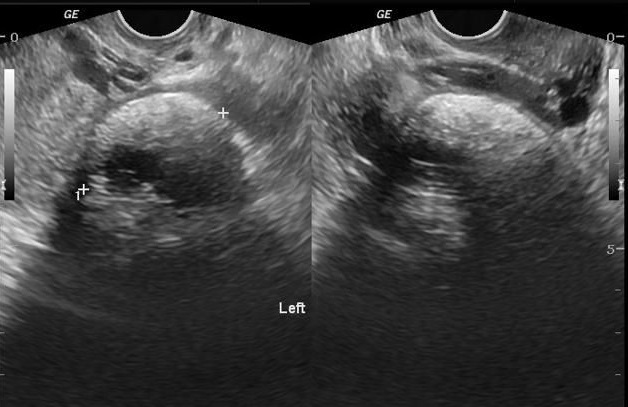

这群日本外科医师原本只是要对这名16岁的女病患进行盲肠切除手术,却发现她其中一个卵巢长了肿瘤,里面甚至还有头发、骨头以及一个小小畸形的脑。

正确的学术名称为成熟囊性畸胎瘤(teratoma)。畸胎瘤是从希腊文”teratos”而来的,这个字是怪物的意思,原因显而易见。畸胎瘤是由一群体内细胞,形成不同的组织包括骨头、神经、头发甚至牙齿。通常畸胎瘤都是被包在囊肿里的良性肿瘤,很容易就能藉由手术移除。

跟其他癌症一样,它们是因为控制细胞成长的讯息发生了错误而导致畸胎瘤。畸胎瘤同时也会发挥像干细胞一样的功能。在这个特殊的例子中,这名日本女孩卵巢内尚未成熟的卵,并没有接受到按兵不动的指令,于是不只是女孩的卵开始分裂,这些新的细胞形成了毛发以及一层细骨头,包覆着一个类似有脑干以及小脑的脑类结构。